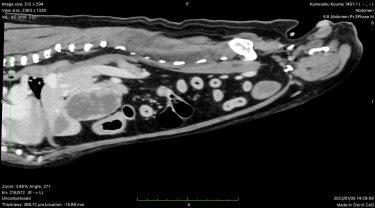

術前検査において、CTを撮影し肝臓の尾状葉に腫瘤が局在することを確認している